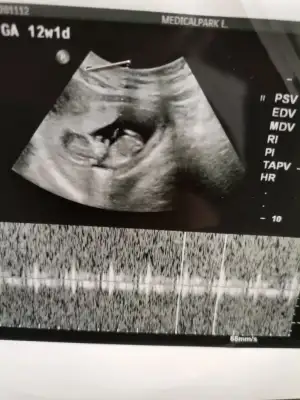

Bende 12 haftalık hamileyim cinsiyetini merak ediyorum banada bakarmısınız

Eklentiler

• IMG_20201211_144150.webp

IMG_20201211_144150.webp

17,3 KB · Görüntüleme: 60

• IMG_20201211_144131.webp

IMG_20201211_144131.webp

14,8 KB · Görüntüleme: 51